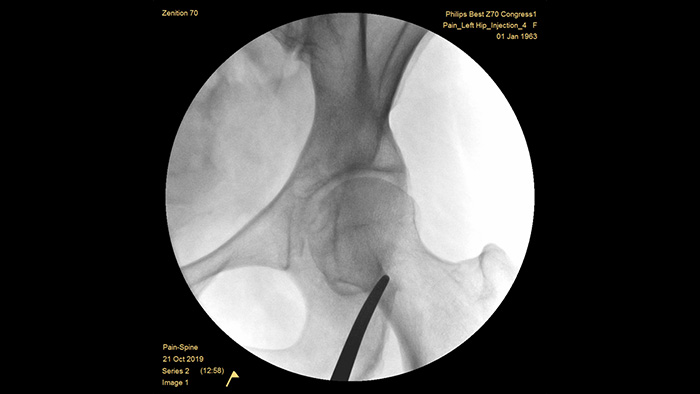

Philips heeft meer dan een halve eeuw ervaring met het ontwikkelen van mobiele C-boogsystemen voor de chirurgische omgeving en heeft een reputatie opgebouwd op het gebied van uitmuntende beeldvorming en dosisefficiëntie. Onze Zenition mobiele chirurgische oplossingen zijn gebaseerd op een uitgebreide aanpak van dosisbeheer. Dit zorgt voor klinisch relevante beeldkwaliteit tijdens interventionele procedures voor pijnbestrijdingstoepassingen, terwijl de blootstelling aan straling van patiënten en medisch personeel efficiënt wordt beheerd.

Met de unieke, vooraf geconfigureerde onderzoeksinstelling voor pijnbestrijding kunnen gebruikers het systeem eenvoudig instellen tijdens interventionele procedures voor pijnbestrijding.

MetalSmart sluit metalen artefacten die worden veroorzaakt door metalen implantaten automatisch uit om, in vergelijking met systemen zonder metaaluitsluiting, een hogere beeldkwaliteit en efficiënte dosiscontrole te bieden voor pijnprocedures en patiënten met metalen implantaten. BodySmart zorgt dat de beeldvorming vaker direct goed is en bevordert de dosisefficiëntie door het meetveld automatisch aan te passen aan het interessegebied.